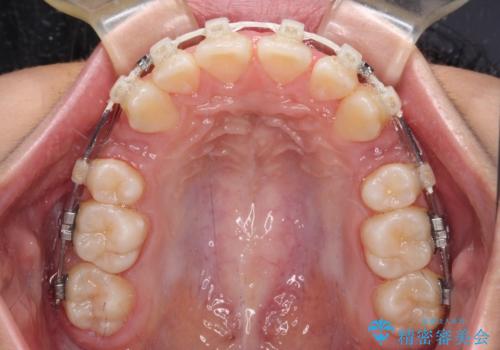

- 矯正装置

- 審美装置

上下左右の第一小臼歯4本を抜歯し、ワイヤー装置での抜歯矯正を行うこととしました。

右側の咬み合わせは、上顎がやや前方位にある状態であったので、通常は補助装置を併用するのですが、高校生ということで補助装置なしで治療を行うこととしました。